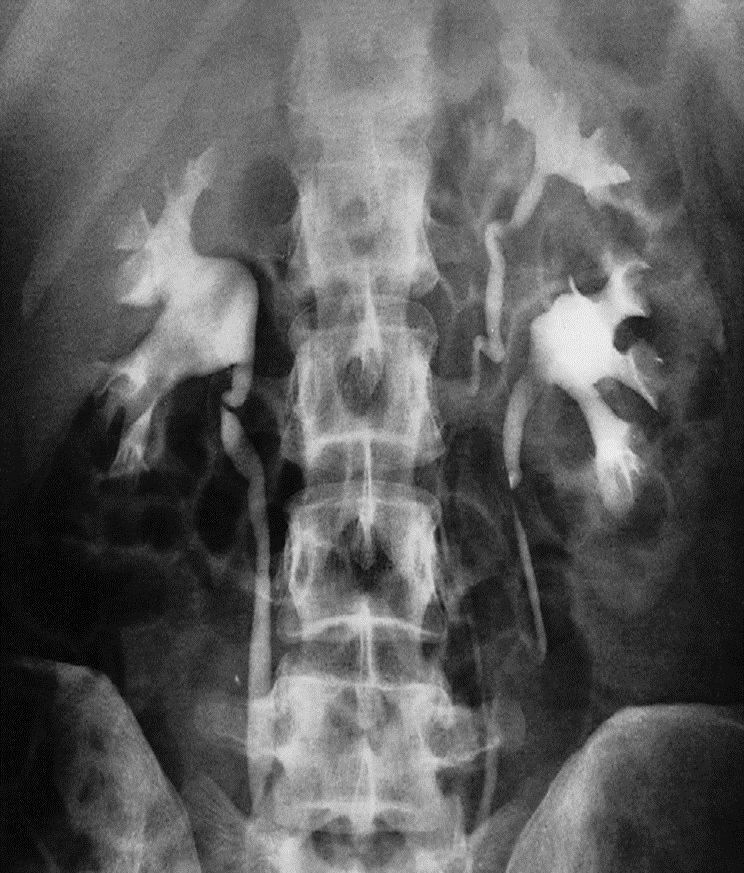

Anomalies Double collecting system

Bifid collecting system. There is a bifid collecting system on the left with the two ureters joining at the level of the transverse process of L5. the left kidney is larger than the right.